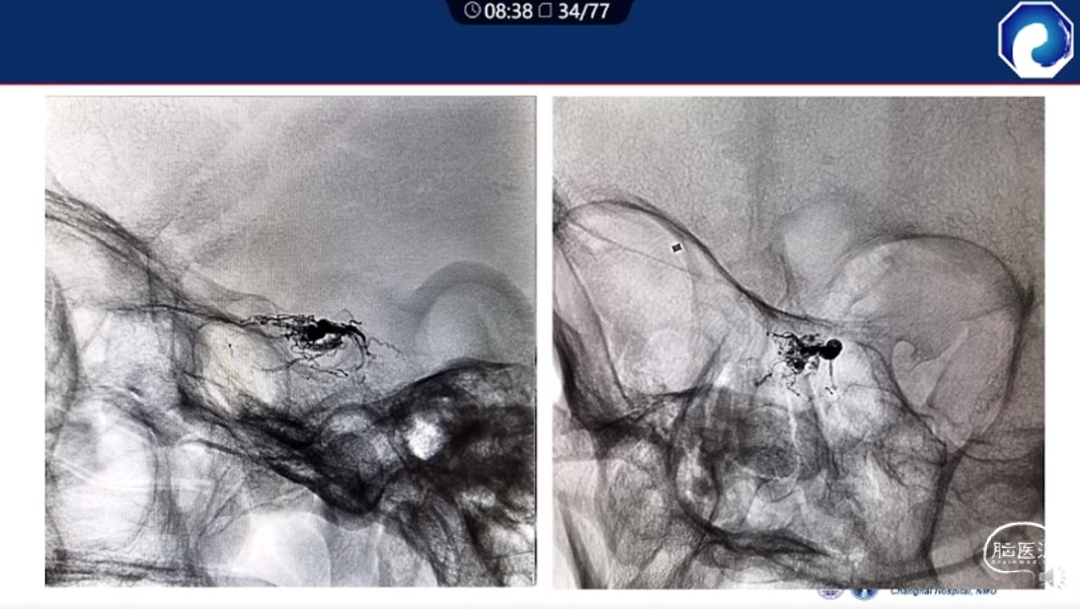

靶向性栓塞可以减少海绵窦分隔的过渡栓塞,有利于减少颅神经并发症,恢复海绵窦的正常引流功能。